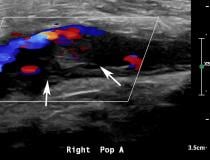

This photo gallery shows the variety of radiological presentations of COVID-19 (SARS-CoV-2) in medical imaging, including computed tomography (CT), radiograph X-rays, ultrasound, echocardiograms and magnetic resonance imaging (MRI). The radiology images show examples of typical COVID pneumonia in the lungs and the numerous complications the virus causes in the body in multiple organs, including the brain, kidneys, heart, abdomen and vascular system.

Ultrasound, especially hand-held ultrasound imaging devices, have become a primary imaging modality for novel coronavirus because of the ease to bag the device and sterilize it after use. CT and mobile X-ray systems are also used as front-line imaging systems for COVID-positive or suspected COVID patients.